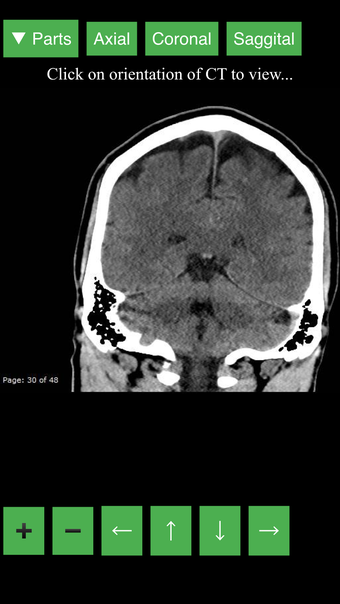

Radiology CT Viewer - полезный инструмент для врачей, медицинских студентов, радиологических техников и других медицинских специалистов, которые хотят узнать больше о человеческом теле и его анатомии. Приложение содержит подробные сечения наиболее важных частей тела. Кроме того, оно содержит интерактивную 3D-модель, которая позволяет вращать, увеличивать и перемещать камеру вокруг изображения, чтобы получить лучший обзор анатомии.

Если вы ищете инструмент, который поможет вам узнать больше о человеческом теле, Radiology CT Viewer - отличный выбор. Он содержит подробные иллюстрации и интерактивную 3D-модель.